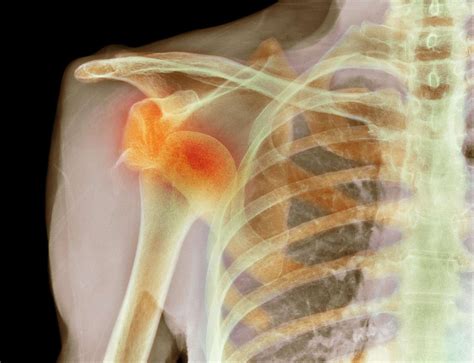

Diagnosing a Dislocated Shoulder Blade

Diagnosing a dislocated shoulder blade involves a combination of physical examination and imaging tests. The healthcare provider will:

• Order imaging tests such as X-rays, CT scans, or MRIs to confirm the diagnosis and assess the extent of the injury.